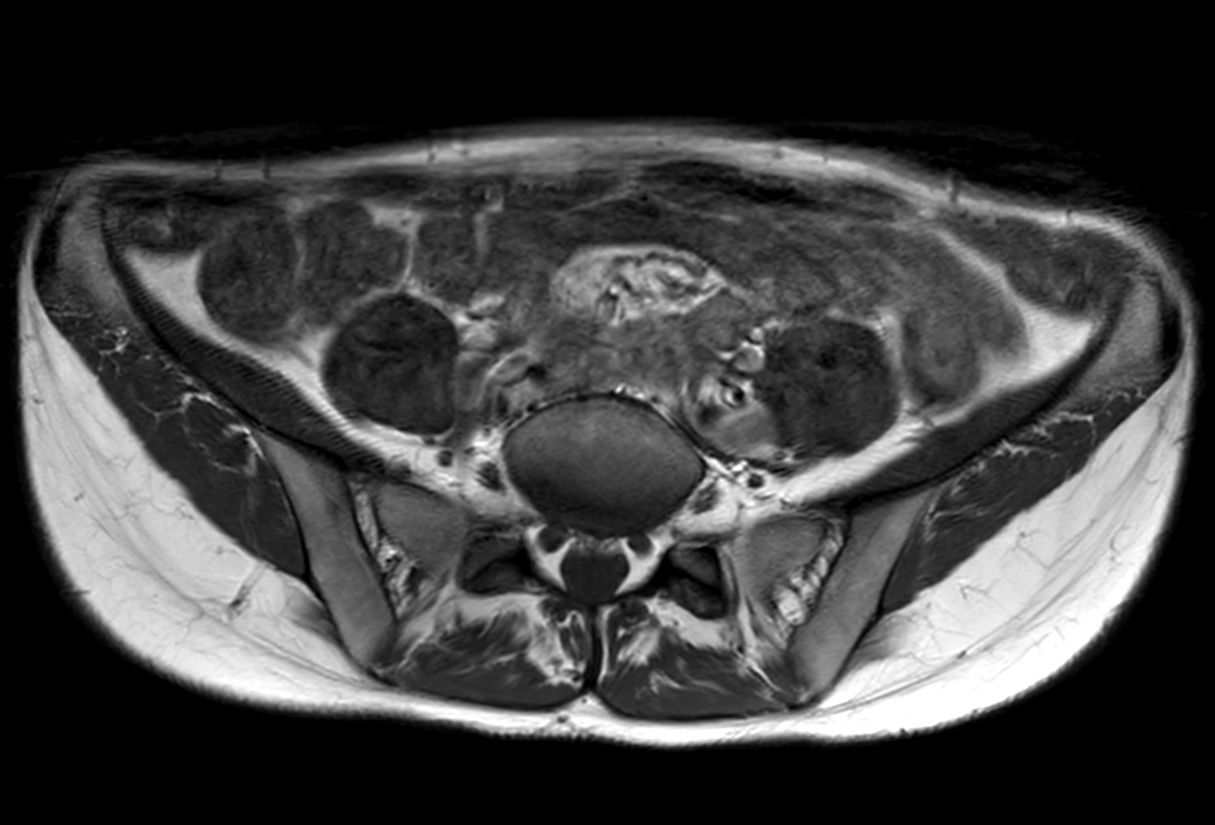

Lumbar Plexus imaging

• Clinical Application